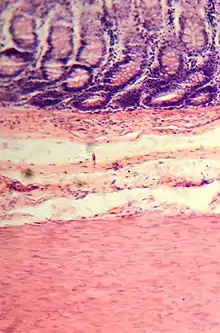

Le gros intestin est le dernier segment du tube digestif des vertébrés. Il fait suite à l’intestin grêle et s’étend de la valvule iléo-cæcale à l’anus ou au cloaque. En anatomie, il est divisé en deux parties : le côlon et le rectum (plus parfois le canal anal)[1],[2].